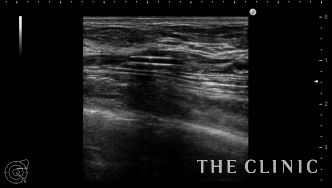

エコーで確認するとかなり厚い被膜が形成されています。

他にも小さなアクアフィリングのしこりを溶解除去しました。